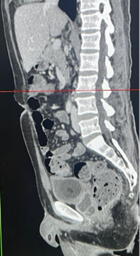

Realizou os exames de imagem abaixo: